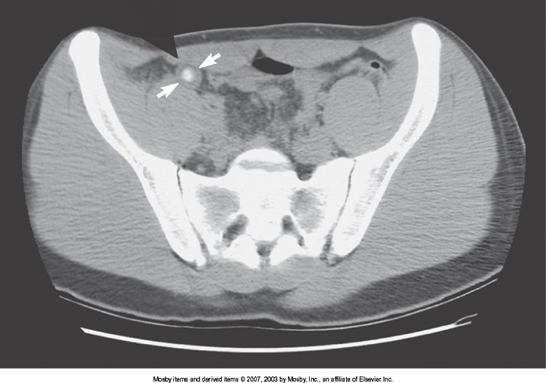

Appendicitis

is the inflammation of the appendix.

Radiological Appearance:

Diameter > 6mm

Peri appendiceal fat stranding

Linear or tubular extension